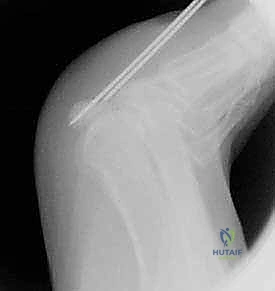

2. التصوير الإشعاعي (X-Rays)

الأشعة السينية هي الخطوة الأولى في التصوير. يتطلب الأمر زوايا تصوير خاصة (Axial Sesamoid View) لرؤية العظام السمسمية بوضوح دون تداخل مع عظام المشطية.

* تحدي تشخيصي: حوالي 10% إلى 30% من الناس لديهم عظمة سمسمية مقسمة خلقياً (Bipartite Sesamoid)، والتي تبدو في الأشعة وكأنها مكسورة. يميز الدكتور هطيف بين الكسر الحقيقي والتقسيم الخلقي من خلال فحص حواف العظمة (حواف الكسر تكون حادة وغير منتظمة، بينما حواف التقسيم الخلقي تكون ناعمة ومستديرة) ومقارنتها بالقدم السليمة.